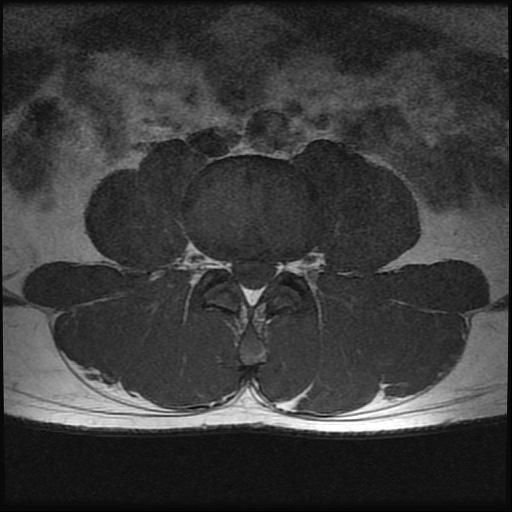

강직성척추염 의심(xray 및 mri 첨부)

인터넷 검색 후 강직성척추염을 알게 되어 말씀 드렸더니 스트레칭??을 해보시고 아닌 것 같은데 걱정이 된다고 하니 x-ray 및 mri를 찍어보자고 하셨습니다. (유전자검사는 채혈 후 대기 중)

xray 및 mri상에도 의심소견이 없다고 하셨는데

사진으로 염증이 있는지 확인 부탁드립니다.

강직성척추염과같은 염증성질환의경우 엑스레이로만은 확인하기가 어려운데요 다른 인자검사라던가 정확한 진단을위한 MRI검사등이 필요할수있습니다

올려주신 엑스레이나 MRI를 참고할 때, 또는 진료시 스트레칭을 통한 허리 및 천장관절의 유연선 평가와 개인에 따라 다르지만 대표적인 강직성 척추염의 증상이 크게 없는 것으로 보아 발생 가능성이 낮을 수 있습니다.

강직성 척추염은 주로 허리의 움직임 제한 및 영상검사에서 관절염에 해당하는 소견과, 혈액검사등에서 염증수치가 증가되어있는 경우가 많지만 이에 해당하지 않는다면 가능성은 낮다고 볼 수 있습니다.